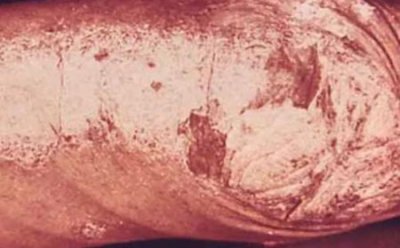

牛皮膚癬是一種慢性、多系統、免疫介導的疾病,主要表現為皮膚和關節。它影響了大約2%的人口。其主要臨床表現是由于皮膚細胞過度增殖而導致的慢性皮膚炎癥,產生毀容、脫屑、紅斑斑塊。牛皮膚癬根據皮膚病變的形態...[詳細]

潤膚劑是用來水合物和保護皮膚天然或人造物質。潤膚劑不僅可以為皮膚添加水分,還可以防止水分蒸發。潤膚劑用于日常皮膚護理,也是治療牛皮癬和其他皮膚病的藥物。雖然可能需要進行一些實驗才能找到適合您的潤膚劑,...[詳細]